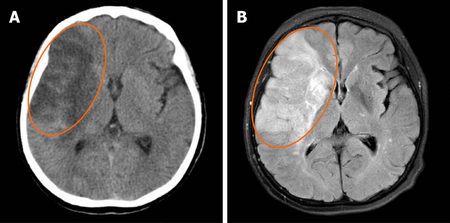

혈전성 뇌경색 MRI 혈전성 뇌경색에서는 환자의 15~50%에서 전구 증상으로 일과성 뇌허혈발작(TIA)을 나타내며 수면 중이나 아침에 일어날 때 발생하는 경우가 많은 것으로 보고됩니다. 증상은 시간에 따라 변화를 보이지만 몇 시간에서 며칠에 걸쳐 개선과 악화가 교차되어 단계적으로 진행되는 경우가 많습니다.

열공성 뇌경색 MRI 뇌의 깊은 부위에 생기는 0.5~15㎜의 경색성 병소로 구멍을 형성하고 있는 것을 열공(lacuna)이라고 합니다. 고령층에 많으며 고혈압에 의한 뇌의 세동맥 경화가 관련된 것으로 알려져 있습니다.보통은 증상이 없지만 부위가 나쁘거나 여러 개 있으면 다양한 증상을 보일 수 있습니다. 예를 들어 거짓 연수 마비, 사지 경직, 종종 걷기, 지능 저하, 정동 장애(무리웃음, 무리울음) 등이 나타납니다.

뇌색전증 MRI 뇌색전증은 뇌경색 속에서도 갑자기 발병하며 활동 시 발병하는 특징이 있습니다. 발생 부위로는 중대뇌동맥의 피질지를 막는 경우가 많으며, 반신마비, 지각장애 외에도 언어장애, 인식불능 등의 고차원적 신경기능장애나 반맹을 동반합니다.

뇌색전증 진행 과정의 후속으로 출혈을 일으키기 쉬운 것도 하나의 특징으로 MRI 검사로 확인할 수 있습니다. 혈전이 초기 위치에서 말초 쪽으로 이동하면 경색 내의 혈관으로 다시 관류되어 출혈이 생기기 쉽습니다. 반면 혈전성 뇌경색으로는 병소가 이동하지 않기 때문에 이러한 후속 출혈은 나타나지 않습니다.뇌색전증에서는 색전의 원인이 될 수 있는 심장 질환을 심전도나 심장 초음파로 찾아내는 것도 필요합니다.